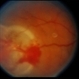

- retinal capillary hemangioblastoma, lipid exudation

- Retinal capillary hemangioblastoma with lipid surrounding.